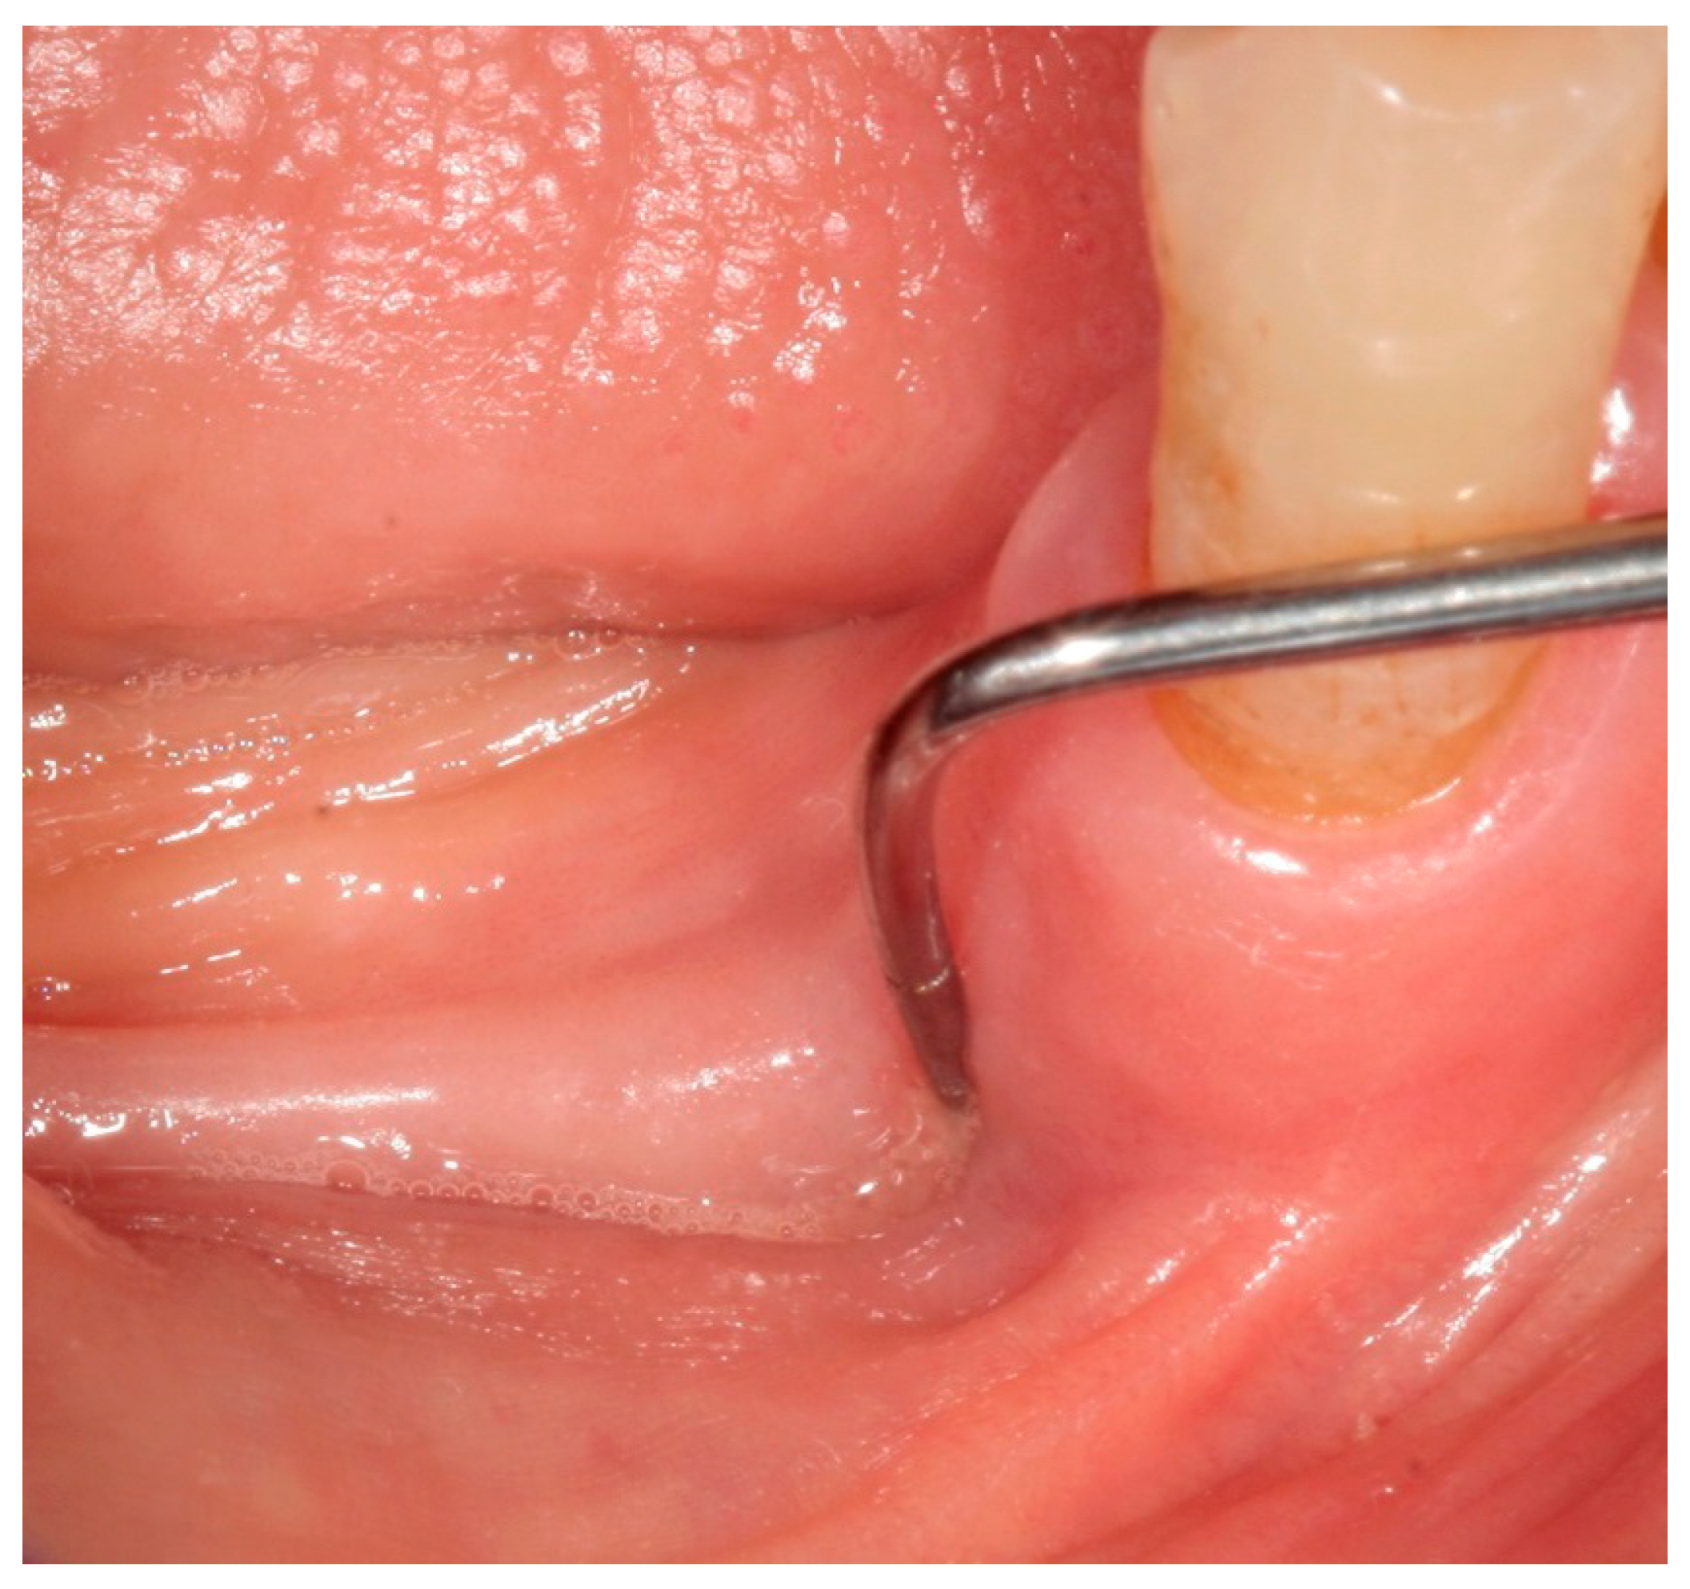

- Bedogni, A.; Fedele, S.; Bedogni, G.; Scoletta, M.; Favia, G.; Colella, G.; Agrillo, A.; Bettini, G.; Di Fede, O.; Oteri, G.; et al. Staging of osteonecrosis of the jaw requires computed tomography for accurate definition of the extent of bony disease. Br. J. Oral Maxillofac. Surg. 2014, 52, 603–608. [Google Scholar] [CrossRef] [PubMed]

- Fedele, S.; Bedogni, G.; Scoletta, M.; Favia, G.; Colella, G.; Agrillo, A.; Bettini, G.; Di Fede, O.; Oteri, G.; Fusco, V.; et al. Up to a quarter of patients with osteonecrosis of the jaw associated with antiresorptive agents remain undiagnosed. Br. J. Oral Maxillofac. Surg. 2015, 53, 13–17. [Google Scholar] [CrossRef] [PubMed]